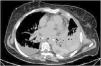

Mujer de 67 años que ingresa en la UCI en shock distributivo refractario. La radiografía de tórax (fig. 1) evidencia hidroneumotórax izquierdo, con separación de hojas pleurales apical de 5cm y desplazamiento mediastínico contralateral (

). La TC (fig. 2) confirma hidroneumotórax, y evidencia empiema pleural y neumomediastino periesofágico en tercio inferior esofágico (). Se realiza drenaje torácico, saliendo aire y líquido de aspecto turbio maloliente, con «abundantes bacterias, gotas de grasa y fibras sugerentes de restos alimenticios». Ante la sospecha de perforación esofágica, se realiza nueva TC con contraste oral (fig. 3) demostrándose extravasación de contraste a nivel del margen lateral izquierdo del esófago inferior, en relación con perforación, y paso de contraste a la cavidad pleural izquierda (). Se realiza cirugía urgente.Contribuciones de autoríaTodos los autores han realizado conjuntamente y a partes iguales la revisión, selección y redacción del artículo.